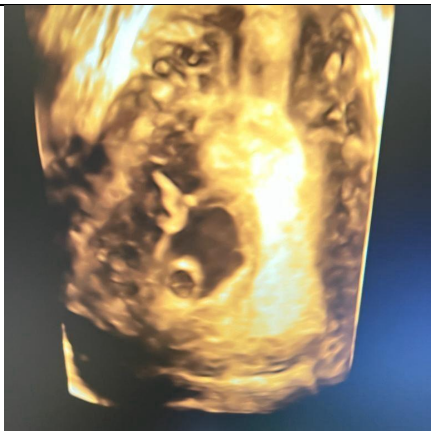

A 16-year-old lady, para 0+2 presented to the emergency department complaining of active vaginal bleeding after medical treatment of missed miscarriage. She had history of two recurrent miscarriages treated by surgical evacuation. Her pregnancy was spontaneous. Her medical history was unremarkable. Clinically she was vitally stable, soft abdomen, no tenderness no palpable masses. Speculum examination was suggestive of normal-looking cervix with bleeding from the os, uniformly enlarged 8 weeks size uterus freely mobile, no cervical movement tenderness, and no adnexal masses. An ultrasound demonstrated a gestational sac about 2.2 cm in diameter. It showed also a yolk sac and a fetal pole of 8 mm without cardiac cavity. Surgical suction and evacuation was performed under ultrasound guidance.  During the evacuation, the gestational sac was noted to be below the suction tube, the procedure was aborted. The intrauterine products were sent for histology which showed fragments of endometrium, blood clots and fibrosed chorionic villi, no evidence of malignancy. Upon reassessment, she was still complaining of the vaginal bleeding. Beta human chorionic gonadotropin was 1450. A Trans abdominal & trans vaginal ultrasound scan showed empty cavity with thick endometrium, a gestational sac below the line of endometrium with a yolk sac and fetal pole without cardiac activity, embedded in the myometrium (Fig.1&2&3&4) .The use of 3-D ultrasound helped in confirming the diagnosis of intramyometrial pregnancy, providing highly informative and detailed imaging to support accurate clinical assessment (Fig.5&6). In view of her parity and future fertility medical treatment was discussed with and accepted by the patient. Methotrexate was administered with a single dose of 50mg given intramuscularly on day 7, the drop was less than 15%. The patient received a second dose of methotrexate .The patient was displaced due to war circumstances. She then continued to have serial pregnancy tests, not able to have quantitative B-HCG test. Her pregnancy test became negative eventually then her menstrual cycle resumed back with regular intervals.

FIG.5

Figure 5